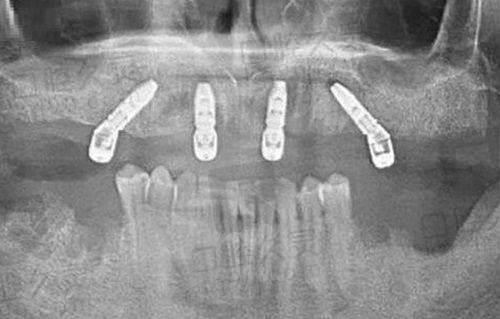

成都安玉牙种植医院紧跟国内外牙种植技术的发展趋势,引进了一系列精良的牙种植设备。如口腔 CT 扫描仪,能够严谨地获取患者口腔的三维影像,为种植手术提供正确的诊断依据;种植导航系统,可帮助医生更精细地定位种植体的位置,提高种植手术的成功几率。